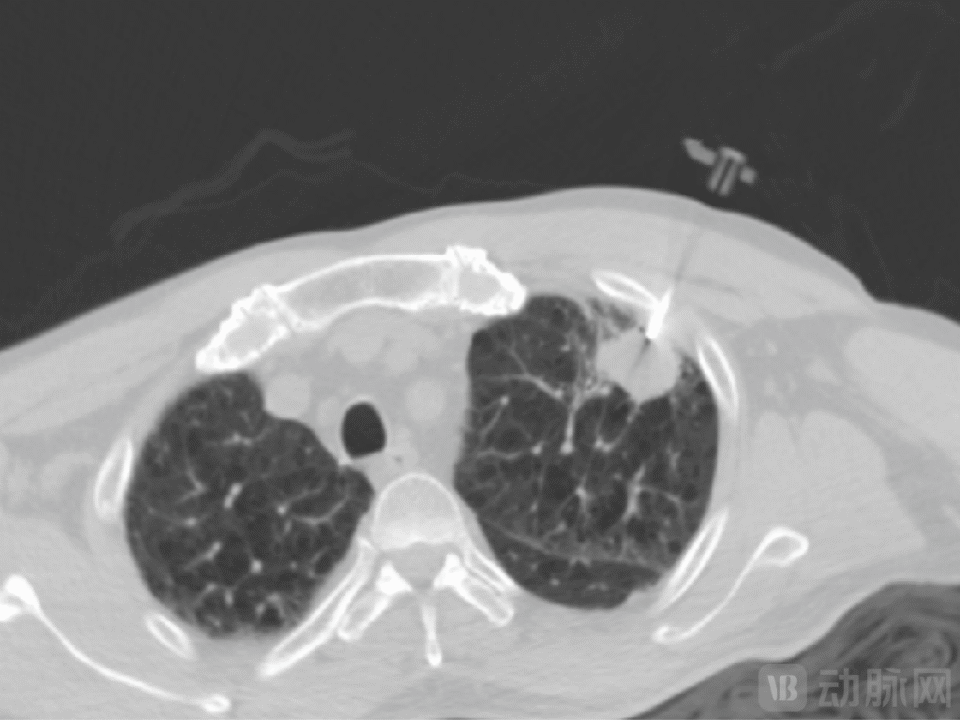

一例患者病例显示,在患者病灶粘连主动脉的情形下,MicrolGT-RoboC执行跨层穿刺规划,自动计算出进针位置及角度,精准穿到病灶。

图片

RoboC规划执行图,图源:微引科技公众号